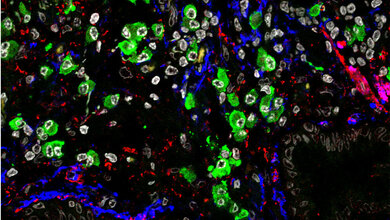

Fehlt NEDD4-2, werden Epithelzellen in den Atemwegen umgestaltet, sodass der Anteil der verschiedenen Zelltypen verändert ist und die Zellen mehr bestimmte Mucine (Bestandteile des Bronchialschleims) produzieren. Kommen veränderte Natriumströme in Epithelzellen und ein verringertes Volumen des Flüssigkeitsfilms hinzu, wird der Abtransport gestört und der Selbstreinigungsprozess der Atemwege eingeschränkt. „Wir konnten somit einen direkten Zusammenhang zwischen dem Fehlen von NEDD4-2 und einer gestörten mukoziliären Clearance sowie der Fehlregulierung des TGFβ-Signalwegs herstellen, zwei Störungen, die nach aktuellen Erkenntnissen in der Pathogenese von IPF eine Rolle spielen“, so Dr. Julia Dürr, Erstautorin der Studie.